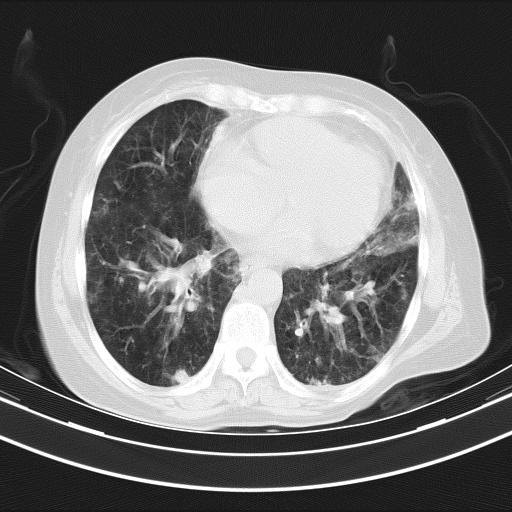

老年女性,嗜睡3天,意识模糊。轻咳,无发热。

双肺多发淡片影,毛玻璃影,,支持支气管肺炎,,建议血气找原因,,嗜睡是否肺性脑病?有没有慢支病史?

1)两肺感染性病变;建议抗炎治疗后复查。2)纵隔淋巴结肿大。3)左侧胸腔积液。